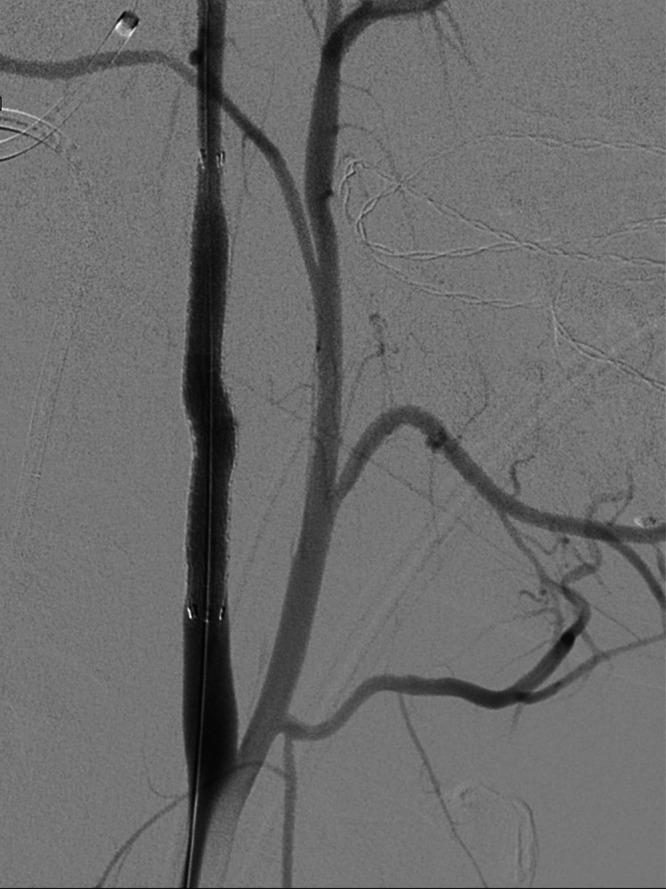

The occlusion was treated with flossing technique via the posterior communicating artery. After successful recanalization from a retrograde approach, the carotid artery occlusion was treated with a covered stent.